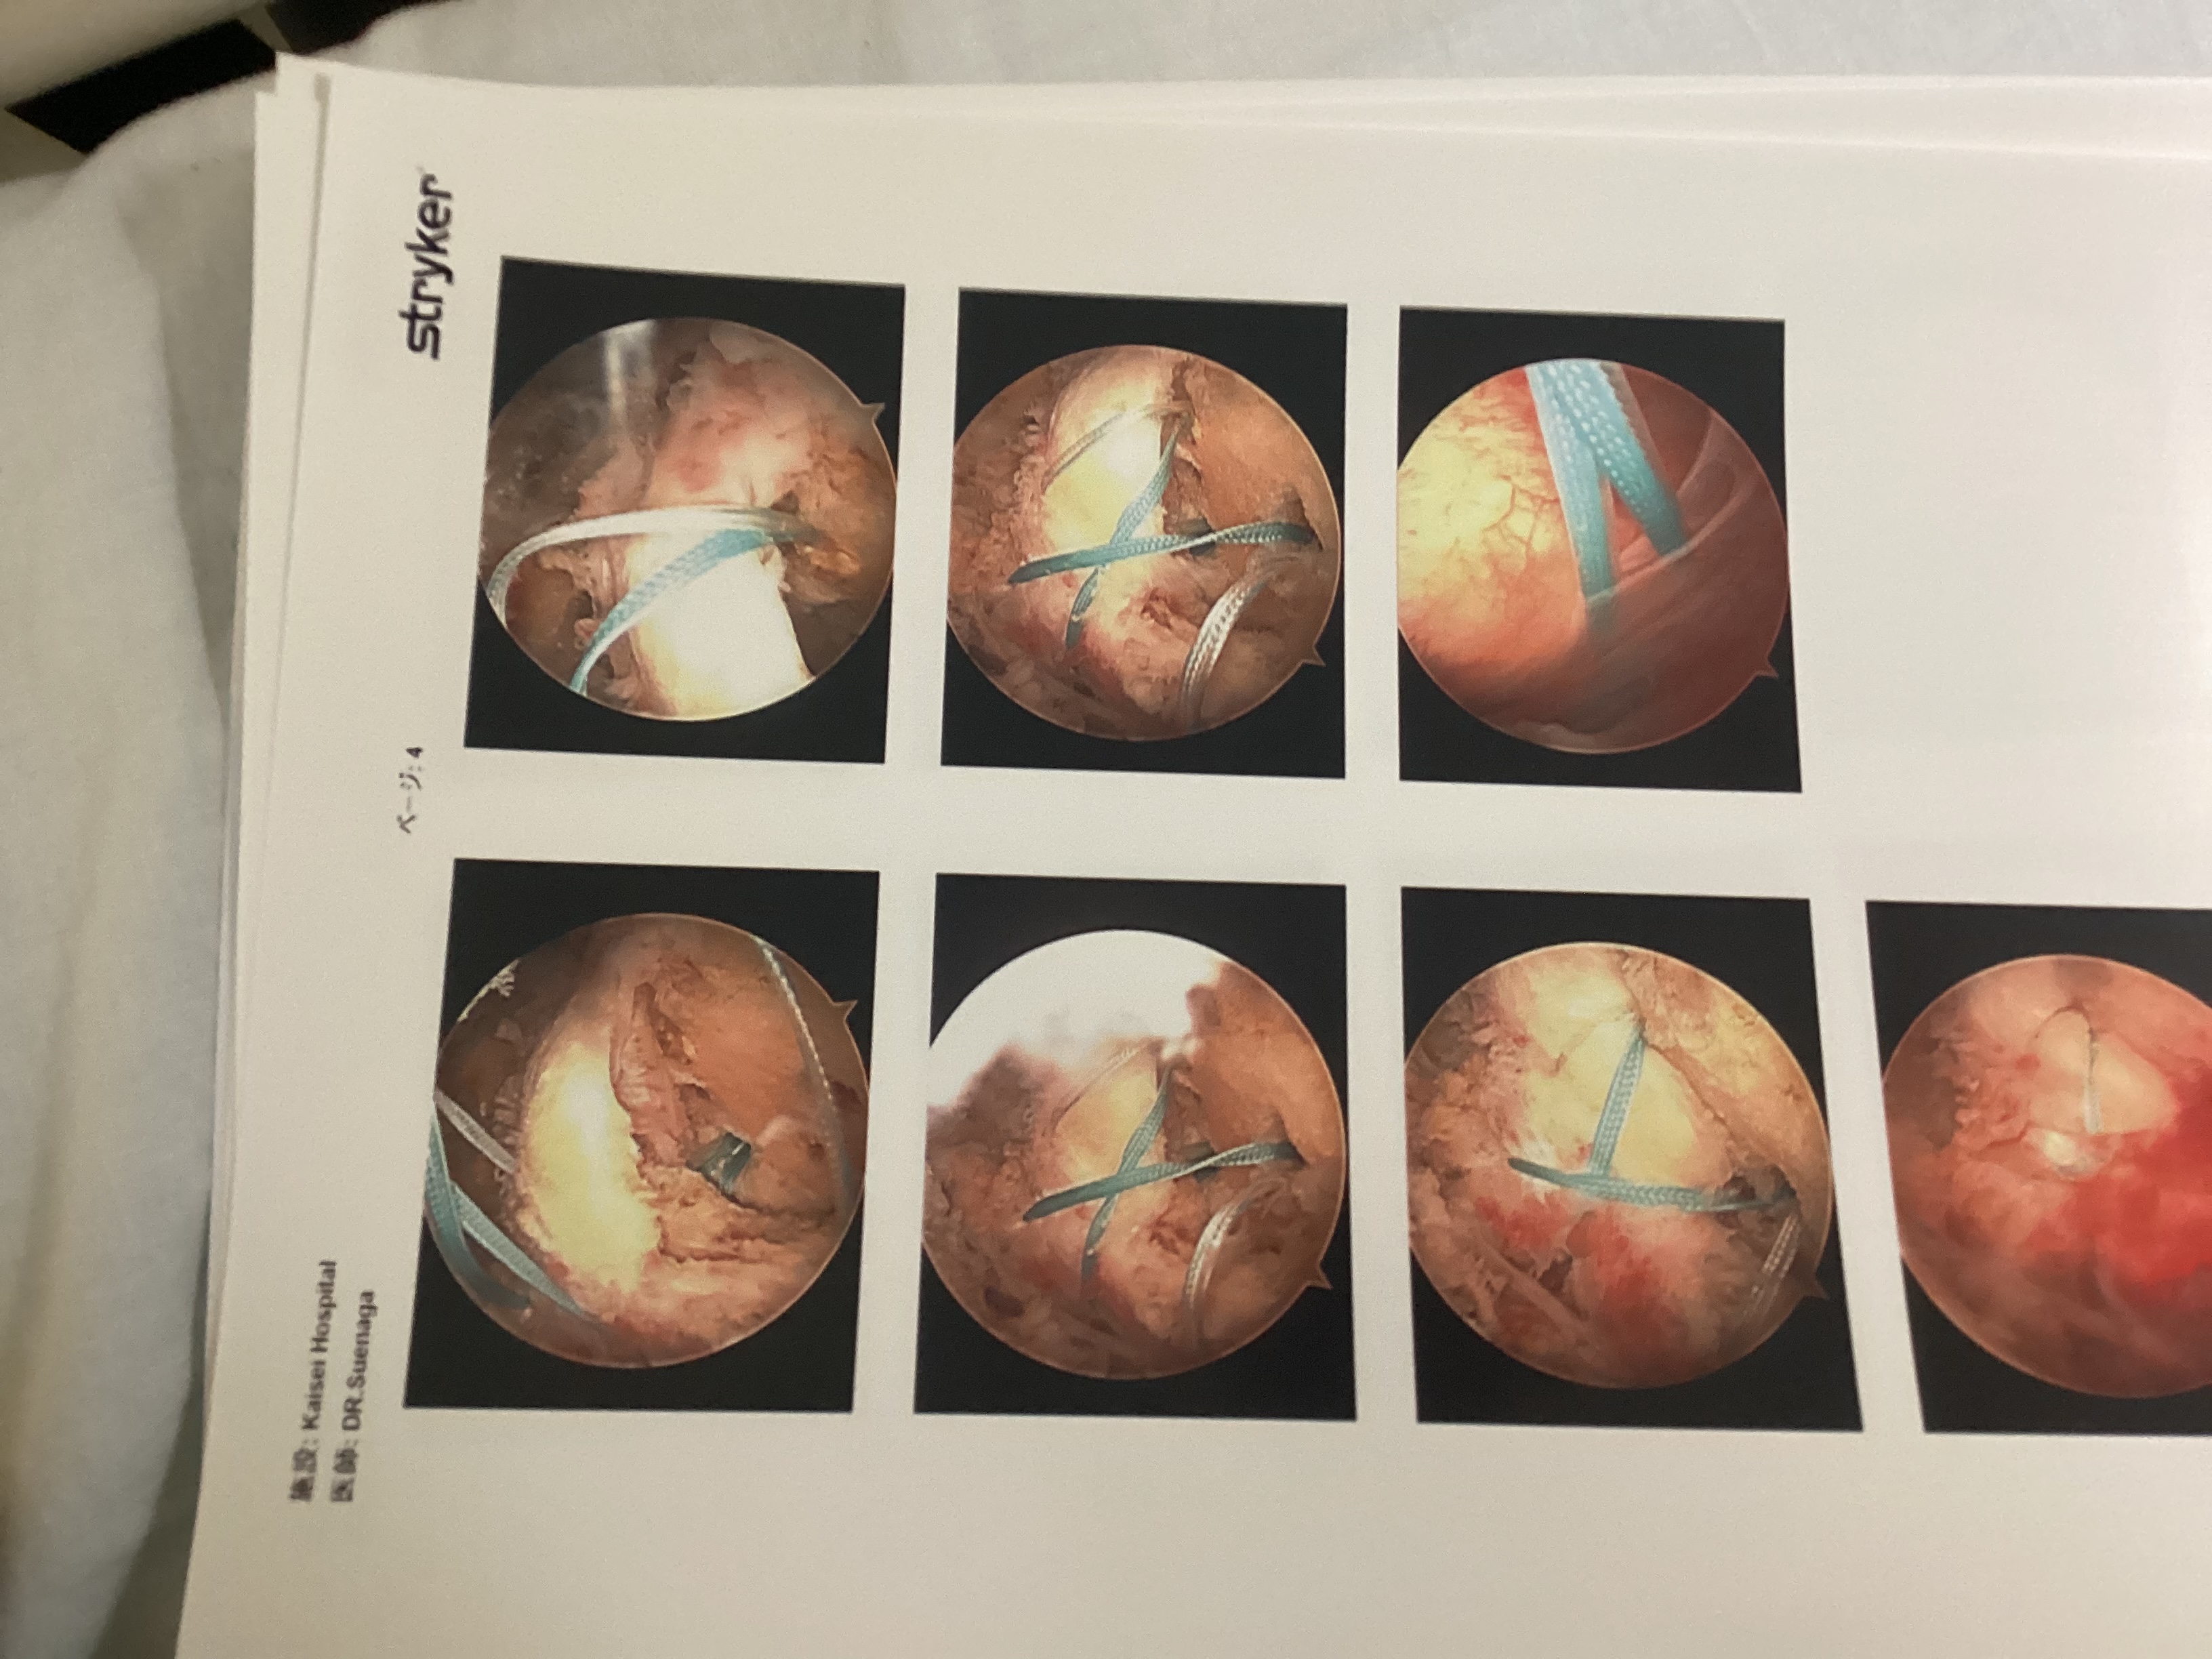

内視鏡手術の写真をもらいました

アンカーを骨に埋めて腱板と縫い合わせてます